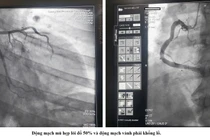

Mặc dù đi dây dẫn qua tổn thương hẹp động mạch vành trái có khó khăn do tổn thương phức tạp nhưng cuối cùng người bệnh vẫn được tái thông mạch vành thành công.

Bệnh nhân nhồi máu cơ tim cấp dị ứng thuốc cản quang được cứu sống ngoạn mục nhờ phương pháp can thiệp đặc biệt.